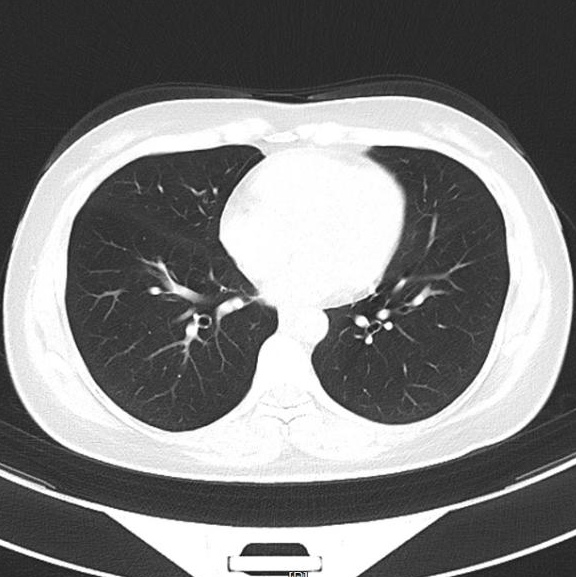

▲治疗前

▲治疗后1月

我们给这位年轻患者口服了靶向药

短短一个月

患者肺部和脑部肿瘤就出现明显退缩